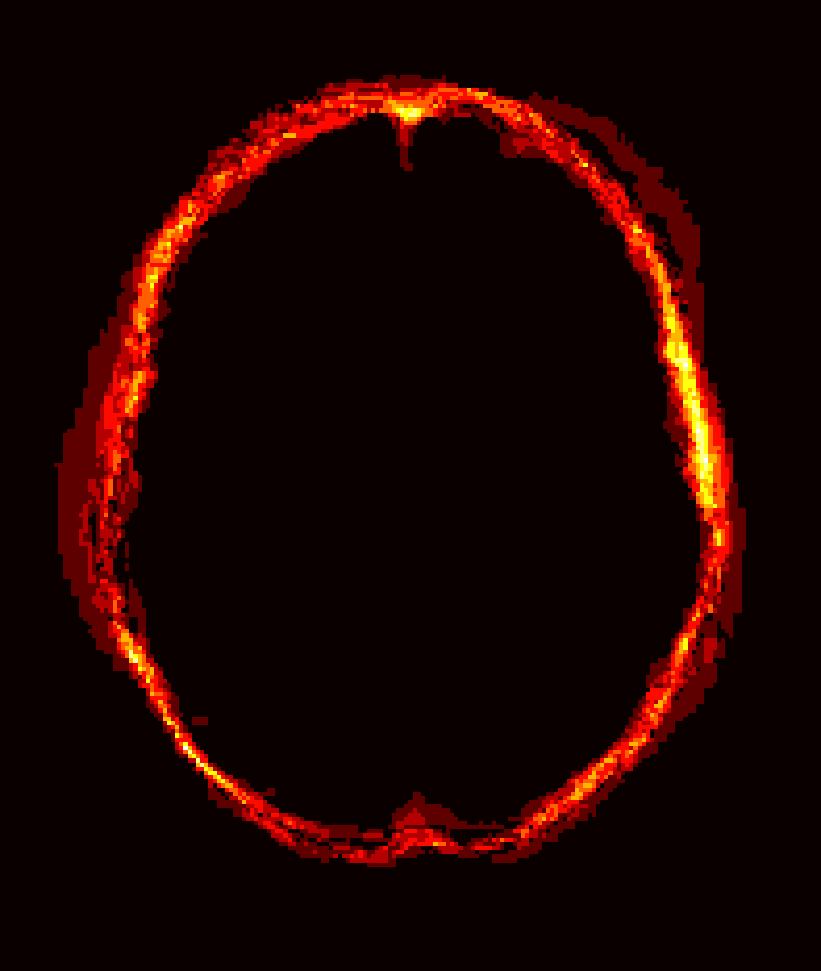

Fig. 1 shows example images from each dataset to illustrate image variability. IBSR and LPBA40 contain images from normal subjects and include large portions of the neck; BRATS has very low out-of-plane resolution; and the TBI dataset contains large pathologies and abnormal skulls.

Refer to caption

Figure 1: Illustration of image appearance variability on a selection of images from each (evaluation) database. From top to bottom: IBSR, LPBA40, BRATS and TBI.